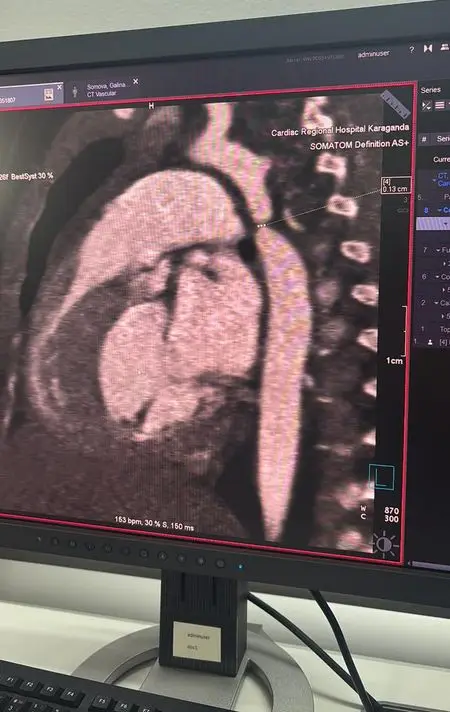

История началась с обычного диагноза. Девочку госпитализировали с пневмонией в многопрофильную больницу №1, и во время обследования врачи обнаружили критическую коарктацию аорты. Это серьёзное заболевание, связанное с сужением аорты, требовало немедленного хирургического вмешательства.

После выявления патологии девочку экстренно перевели в Кардиоцентр. Врачи провели консилиум и приняли решение о необходимости операции, которая проходила в рамках мастер-класса с участием ведущих кардиохирургов страны. Операция длилась почти пять часов и включала резекцию коарктации аорты с наложением анастомоза "конец в конец".

Во время вмешательства также был обнаружен открытый артериальный проток, который был успешно легирован. Кардиохирург Галымжан Утегенов отметил, что операция была технически сложной, но прошла в плановом режиме. В настоящее время состояние ребёнка стабильно, и она находится под наблюдением врачей.